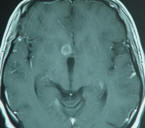

MRI of the brain was done

07-December-2009 and MRA of the brain with MRI

of the brain with contrast repeated

08-December-2009 showing the subependymar mass

in the region between the head of the right

caudate nucleus and the anterior commissure.

There was no aneurysm and there was still

enhancement of the ring around the mass, which

slightly shrunken in comparison to the MRI

performed 17-Novemeber-2009. |